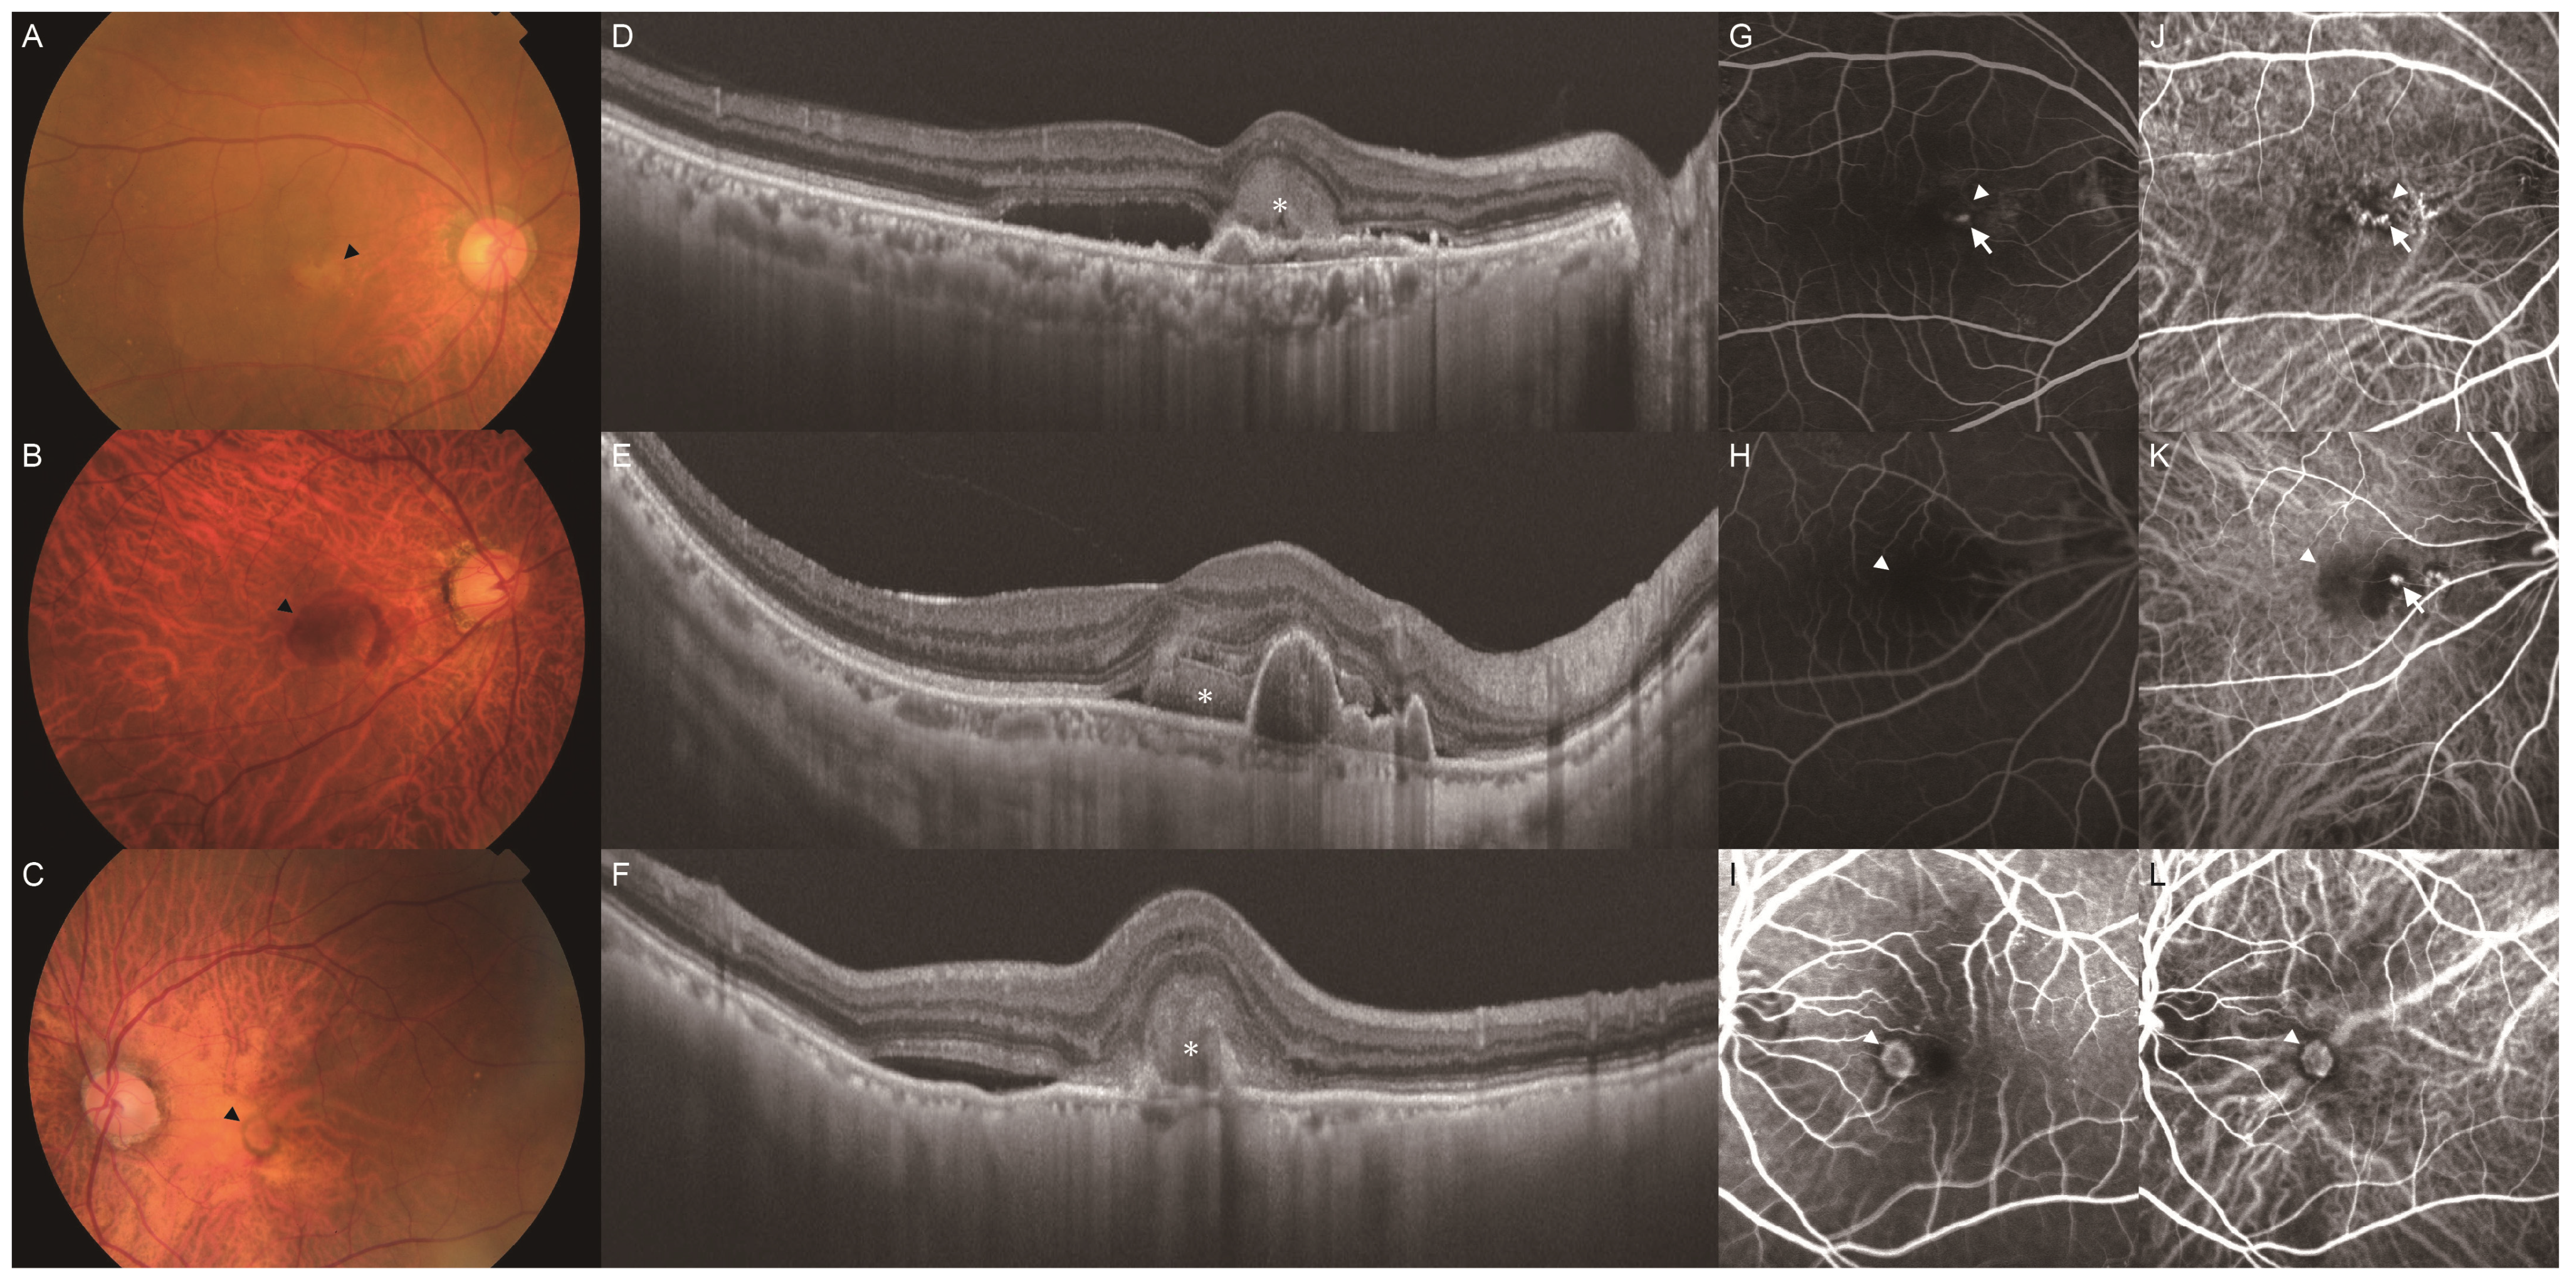

Clinical Characteristics of Punctate Hyperfluorescence Spots in the Fellow Eye of Patients with Unilateral Macular Neovascularization with No Drusen

- Tsujikawa, A.; Ojima, Y.; Yamashiro, K.; Ooto, S.; Tamura, H.; Nakagawa, S.; Yoshimura, N. Punctate hyperfluorescent spots associated with central serous chorioretinopathy as seen on indocyanine green angiography. Retina 2010, 30, 801–809. [Google Scholar] [CrossRef] [PubMed]

- Park, S.J.; Kim, B.H.; Park, K.H.; Woo, S.J. Punctate hyperfluorescence spot as a common choroidopathy of central serous chorioretinopathy and polypoidal choroidal vasculopathy. Am. J. Ophthalmol. 2014, 158, 1155–1163. [Google Scholar] [CrossRef] [PubMed]

- Kim, H.; Lee, J.H.; Kwon, K.Y.; Byeon, S.H.; Lee, S.C.; Lee, C.S. Punctate hyperfluorescent spots associated with polypoidal choroidal vasculopathy on indocyanine green angiography. Ophthalmic. Surg. Lasers Imaging Retina. 2015, 46, 423–427. [Google Scholar] [CrossRef]

- Kang, H.G.; Han, J.Y.; Kim, M.; Byeon, S.H.; Kim, S.S.; Koh, H.J.; Lee, C.S. Pachydrusen, choroidal vascular hyperpermeability, and punctate hyperfluorescent spots. Graefes Arch. Clin. Exp. Ophthalmol. 2021, 259, 2391–2400. [Google Scholar] [CrossRef]

- Matsumoto, H.; Hoshino, J.; Mukai, R.; Nakamura, K.; Kishi, S.; Akiyama, H. Chronic choriocapillaris ischemia in dilated vortex vein region in pachychoroid neovasculopathy. Sci. Rep. 2021, 11, 16274. [Google Scholar] [CrossRef]